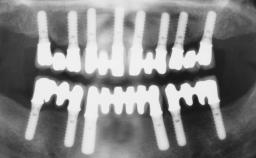

Surgical treatment of a 68-year-old female patient who experienced failure of her conventional bridge in the right maxilla. After removal of the compromised abutment teeth and a healing period of 6 weeks, a sinus floor elevation procedure using the lateral window technique and a composite graft to correct the insufficient bone height is carried out.

Two dental implants are placed in the same surgical session. The case concludes with the presentation of the final fixed dental prosthesis with a distal cantilever unit.

The 1-year follow-up radiographs demonstrate successful sinus floor elevation and stable bone crest levels around both implants, leading to a favorable long-term prognosis of the implant-supported prosthesis.

# of Implants 2

Type of Implants One-Piece